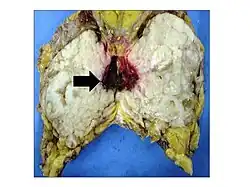

Gross image of an excised phyllodes tumor.